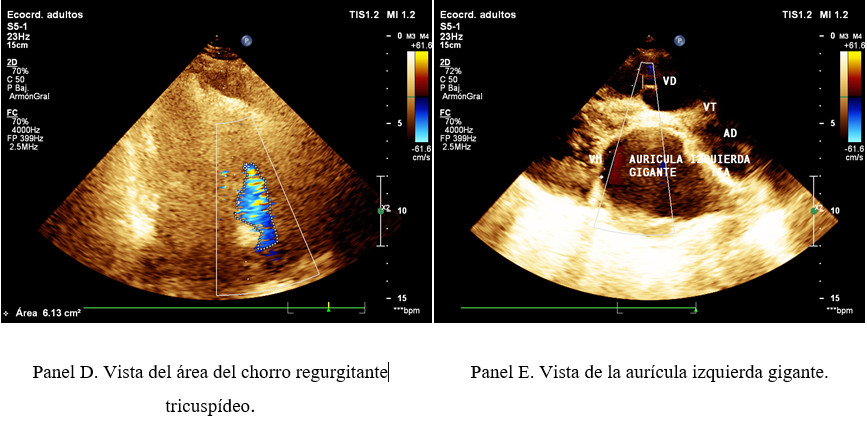

Ecocardiograma,  FE 28%, hay hipertension pulmonar, insuficiencia mitral severa.